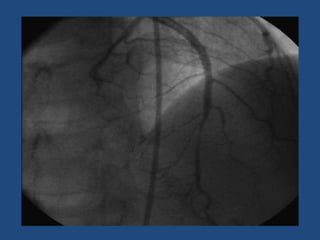

• Inestables y/o con flujo distal el tratamiento con angioplastia

coronaria con implante de stent es lo indicado en disecciones

localizadas.

• IVUS asegura que la guía esté en la verdadera luz y que tras el

implante del stent no se haya producido una propagación de

la disección o protrusión de trombo por uno de los extremos.